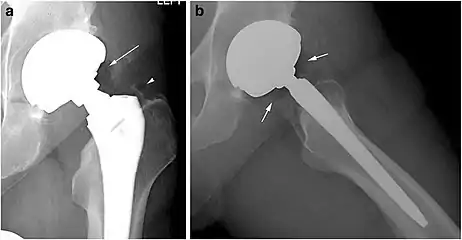

Joints

Pneumarthrosis is the presence of air in a joint. Its presentation on radiography is a radiolucent cleft often called a vacuum phenomenon, or vacuum sign.[7] Pneumarthrosis is associated with osteoarthritis and spondylosis.[8]

Pneumarthrosis is a common normal finding in shoulders[7] as well as in sternoclavicular joints.[9] It is believed to be a cause of the sounds of joint cracking.[8] It is also a common normal post-operative finding at least after spinal surgery.[10] Pneumarthrosis is extremely rare in conjunction with fluid or pus in a joint, and its presence can therefore practically exclude infection.[8]